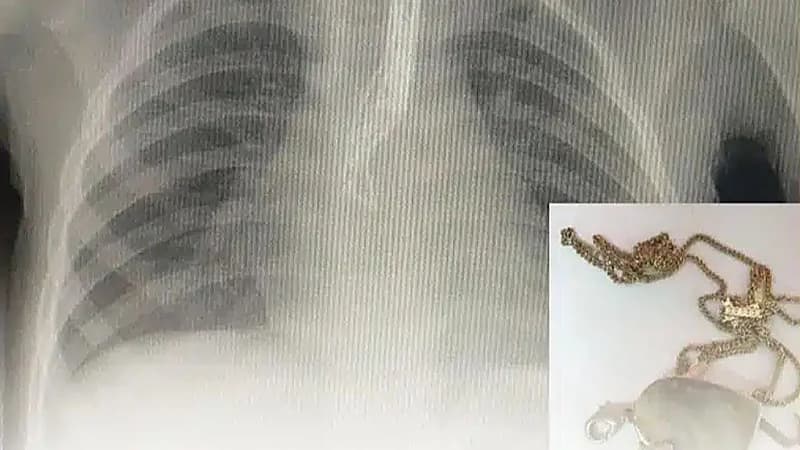

تمكنت الفرق الطبية بطوارئ مستشفى أحد العام، عضو تجمُّع المدينة المنوّرة الصحي، من إنقاذ حياة طفلة ابتلعت جسماً غريباً استقر في الجزء العلوي من المريء؛ حيث تمّ استخراجه في وقت وجيز باستخدام المنظار.

وتفصيلاً، حضرت الطفلة البالغة من العمر أربعة أعوام إلى طوارئ مستشفى أحد عن طريق الإسعاف رفقة عائلتها بعد ابتلاعها جسماً غريباً، لتباشر في حينها فرق الطوارئ الإجراءات الطبية اللازمة التي أظهرت وجود “قلادة” في الجزء العلوي من المريء .

وعلى الفور تم تحضير الطفلة، بشكلٍ طارئ، لاستخراج القطعة تحت التخدير العام وذلك باستخدام المنظار والأدوات اللازمة.

وأكد تجمُّع المدينة المنورة الصحي، أنه تم استخراج القطعة دون أي مضاعفات أو آثار جانبية واستقرت حالة الطفلة وغادرت المستشفى بصحة جيدة بعد الاطمئنان على سلامتها.